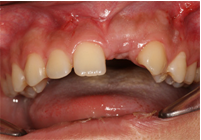

Phục hình răng trên implant

![]() |

| Gắn răng sứ trên Implant R24 |